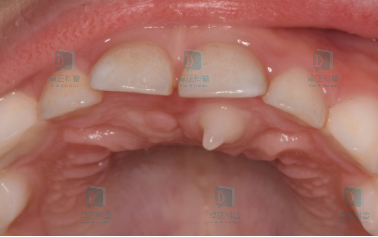

图片

多见于乳前牙,是一种比较常见的牙齿发育异常,也就是两颗牙在发育的时候融合在了一起,萌出后可以看到两颗牙之间有缝隙,就像一个小豁口。

融合牙除了锯齿状的,还有各种各样的其他形状,比如蝴蝶状、山丘状